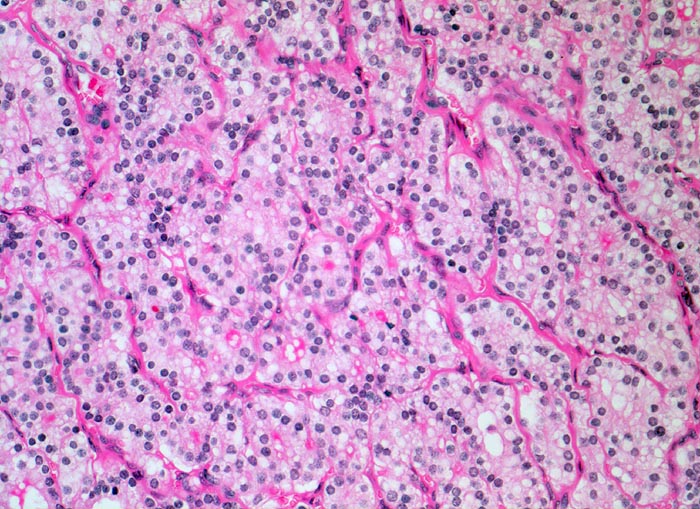

• Zeichen gesteigerter hormoneller Aktivität im Adenom:

• Kleine Drüsenlumina.

• Teils mehrreihiges kubisches bis zylindrisches Epithel.

• Fehlendes oder nur spärliches helles Kolloid mit zahlreichen Resorptionsvakuolen.